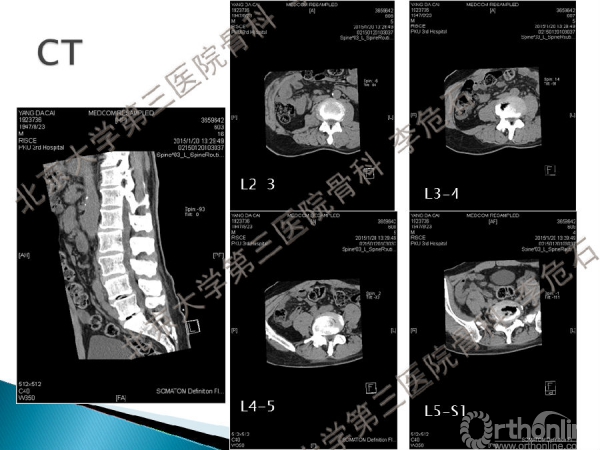

一位67岁的男性患者,因间断腰痛4年,加重伴双下肢放射痛、间歇性跛行12个月而就诊,当地医院诊断为“腰椎管狭窄症”,行止痛、营养神经等治疗后无明显缓解,为进一步诊治于2015年1月入北医三院治疗。

入院检查诊断为:腰椎管狭窄症、腰椎间盘突出(L3-5)、退变性滑脱、腰椎退变性侧弯、高血压病、阑尾切除术后和心律失常。

分别于2015年1月和8月两次入院手术,分析第一次手术疗效不佳的原因,作者认为在重建矢状位平衡时需考虑以下因素:固定融合范围;骨盆-腰椎矢状位形态顺列拟合关系;术前矢状位失平衡:脊柱曲度变化、疼痛、肌肉,评估腰背部肌肉功能。